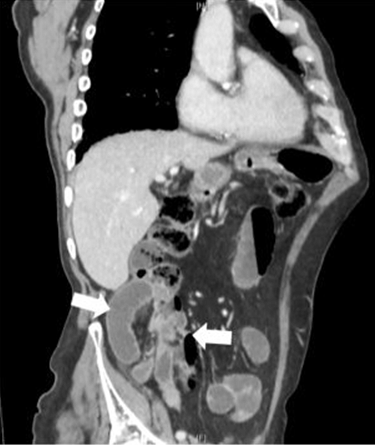

A computed tomography scan was performed, revealing a localized incarcerated segment of small bowel lateral to the cecum in the right paracolic gutter with upstream dilatation of small bowel loops lying anterior to the ascending colon. The associated localized mesenteric congestion and fluid surrounding the localized segment of small bowel in the right iliac fossa were suggestive of a paracecal hernia.

Figure 1: Cluster of small bowel loops incarcerated lateral to the cecum in the right paracolic gutter.

Figure 2: Stretched mesentery, disproportionate edema and inter-loop fluid in affected segment-concern for vascular compromise.

When there is diagnostic uncertainty, or if internal hernia is suspected, computed tomography scan is the preferred investigation of choice. Aside from confirming the diagnosis, this readily available imaging provides information about the presence of strangulation and ischemia as an aid to preoperative planning. The presence of a cluster of dilated small bowel loops, a transition point lateral to the cecum and congestion of mesenteric vessels raise suspicion for an obstructing paracecal hernia. The cecum can sometimes be seen to have been displaced anteromedially. Other imaging modalities such as plain X-ray films and contrast studies often provide limited information and may result in delayed diagnosis subsequently increasing the risk of complications [2][4][6]